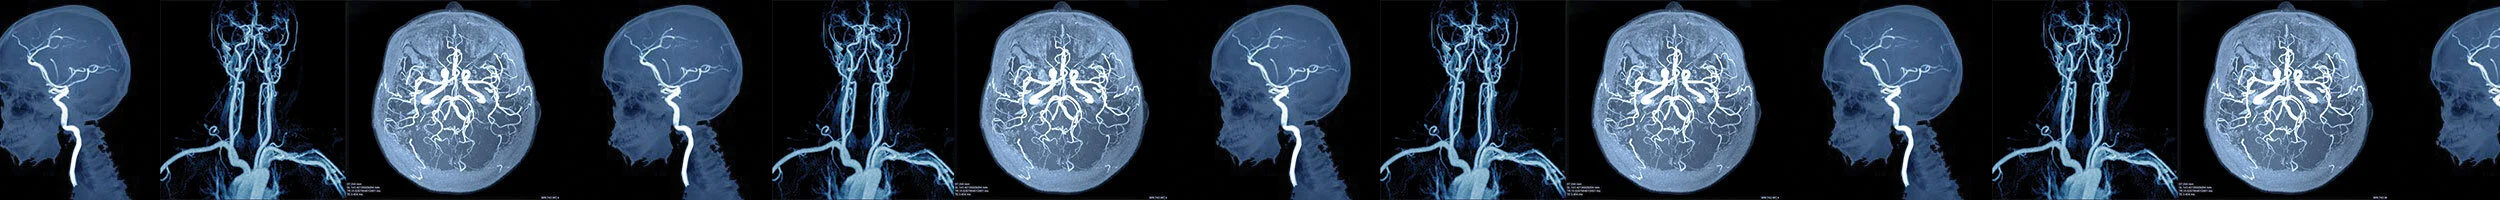

Refer a Brain Aneurysm case